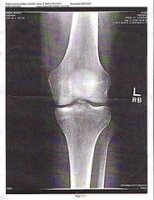

Reumatyzm groźną chorobą cywilizacyjną

Bóle stawów są problemem, z którym zmaga się wiele osób. Według statystyk są one najczęstszą przyczyną zgłaszania się chorych do lekarza. Dotykają zarówno młodych, jak i osoby w podeszłym wieku. Czy bóle stawowe mogą być objawem poważniejszej choroby?